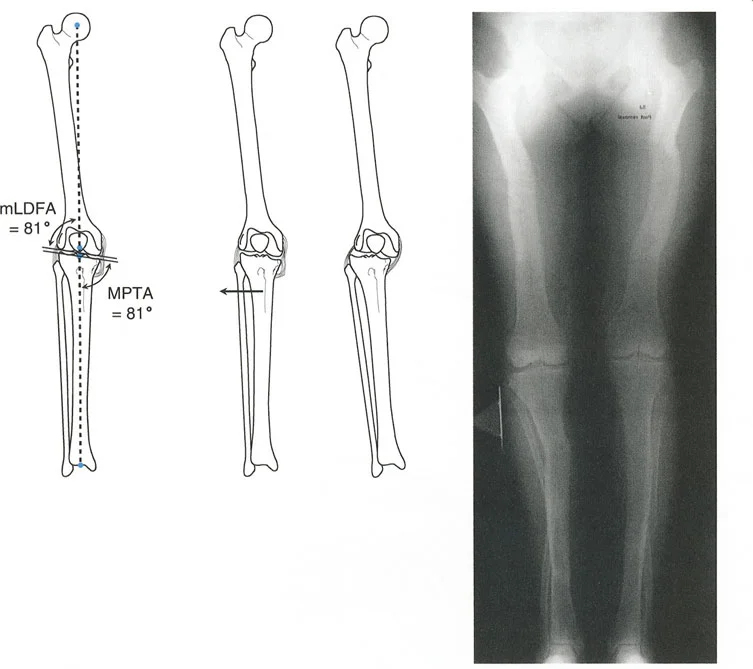

انحراف المحور الميكانيكي (MAD): مقياس الضرر

بناءً على ملاحظات التشريح الطبيعي، تُعتبر مفاصل الطرف السفلي متوازية بشكل طبيعي. أي تشويه لهذه العلاقة يؤثر بشكل متوقع على نقل الأحمال. بينما يمكن لمفصل الورك (كونه مفصلاً كرويًا متطابقًا للغاية) أن يستوعب بعض التغيير في اتجاه الحمل، ومفصل الكاحل محمي بحركة تعويضية معقدة للمفصل تحت الكاحل، فإن الركبة معرضة بشكل استثنائي للتغيرات في المستوى التاجي. إنها مفصل مفصلي يعتمد بشكل كبير على أربطته الجانبية والغضاريف الهلالية لإدارة الأحمال غير المتساوية.

عندما يؤدي تشوه المستوى التاجي إلى اختلال المحاذاة المحورية، فإن محور تحمل الوزن يمر إما وسطيًا أو جانبيًا لمركز الركبة. تُقاس القيمة المطلقة لهذا الانحراف باسم انحراف المحور الميكانيكي (Mechanical Axis Deviation - MAD).

كيفية قياس MAD:

- ارسم المحور الميكانيكي للطرف السفلي (خط مستقيم من مركز رأس الفخذ إلى مركز سطح الساق).

- ارسم قطعة خطية عمودية تمتد من خط المحور الميكانيكي هذا إلى المركز الهندسي الدقيق لمفصل الركبة (نقطة المنتصف بين شوكتي الساق).

- طول هذه القطعة العمودية، المقاس بالملليمترات، هو MAD.

يعكس حجم MAD بشكل مباشر حجم نقل الإجهاد المتغير عبر الركبة. يُعد قياس MAD متفوقًا بشكل كبير على مجرد قياس الزوايا الإجمالية للطرف لأنه يأخذ في الاعتبار التشوهات من أي نوع — بما في ذلك الدوران، الانتقال، والزاوية — ويترجمها إلى قيمة ميكانيكية حيوية واحدة ذات صلة سريريًا.

مبادئ بالي لاتجاه المفصل (Paley's Principles of Joint Orientation)

زوايا اتجاه المفصل القياسية (بالي):

| اختصار الزاوية | الاسم الكامل بالإنجليزية | القيمة الطبيعية | الأهمية السريرية |

|---|---|---|---|

| LPFA | Lateral Proximal Femoral Angle | 90° (89.9° ± 5.2°) | تقييم تقوس/فحج عظم الفخذ القريب (مثل جنف الورك). يوجه عمليات قطع عظم الفخذ القريب. |

| mLDFA | Mechanical Lateral Distal Femoral Angle | 88° (87.8° ± 1.6°) | يحدد خط المفصل لعظم الفخذ البعيد. حاسم لعمليات قطع عظم الفخذ البعيد (DFO) واستبدال مفصل الركبة الكلي (TKA). |

| MPTA | Medial Proximal Tibial Angle | 87° (87.2° ± 1.5°) | يحدد خط المفصل لعظم الساق القريب. المقياس الأساسي لعملية قطع عظم الساق العالية (HTO). |

| JLCA | Joint Line Convergence Angle | 0° - 2° | يقيم التشوه داخل المفصل، فقدان الغضروف، أو رخاوة الأربطة الجانبية. |